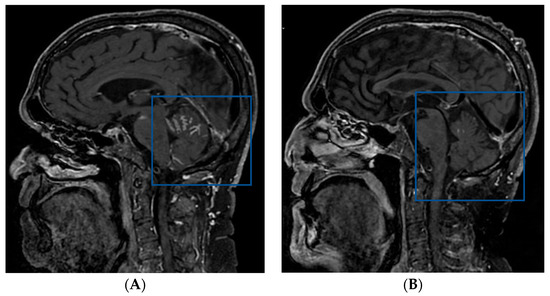

2.2. Case 2

2.3. Case 3